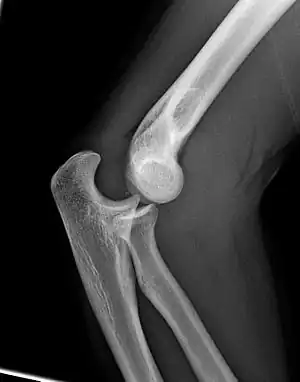

Normal radiograph; right picture of the straightened arm shows the carrying angle of the elbow

When the arm is extended, with the palm facing forward or up, the bones of the upper arm (humerus) and forearm (radius and ulna) are not perfectly aligned. The deviation from a straight line occurs in the direction of the thumb, and is referred to as the "carrying angle".[22]

The carrying angle permits the arm to be swung without contacting the hips. Women on average have smaller shoulders and wider hips than men, which tends to produce a larger carrying angle (i.e., larger deviation from a straight line than that in men). There is, however, extensive overlap in the carrying angle between individual men and women, and a sex-bias has not been consistently observed in scientific studies.[23]

The angle is greater in the dominant limb than the non-dominant limb of both sexes,[24] suggesting that natural forces acting on the elbow modify the carrying angle. Developmental,[25] aging and possibly racial influences add further to the variability of this parameter.